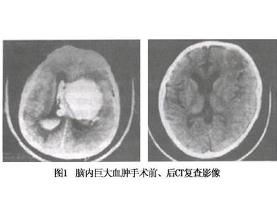

注意與腦幹損傷及丘腦下部損傷相鑑別CT掃描可以明確病變情況。

丘腦下部損傷往往與嚴重腦挫裂傷、腦幹損傷或顱內高壓同時伴發,臨床表現複雜,常相互參錯,故較少單純的典型病例。一般只要有某些代表丘腦下部損傷的徵象,即可考慮伴有此部損傷。近年來通過CT和MRI檢查,明顯提高了丘腦下部損傷的診斷水平。不過有時對三腦室附近的灶性出血,常因容積效應影響不易在CT圖像上顯示,故對於丘腦下部仍以MRI為佳,即使只有細小的散在斑點狀出血也能夠顯示,於急性期在T2加權像上為低信號,在T1加權像則呈等信號。亞急性和慢性期T1加權像上出血灶為清晰的高信號,更利於識別。